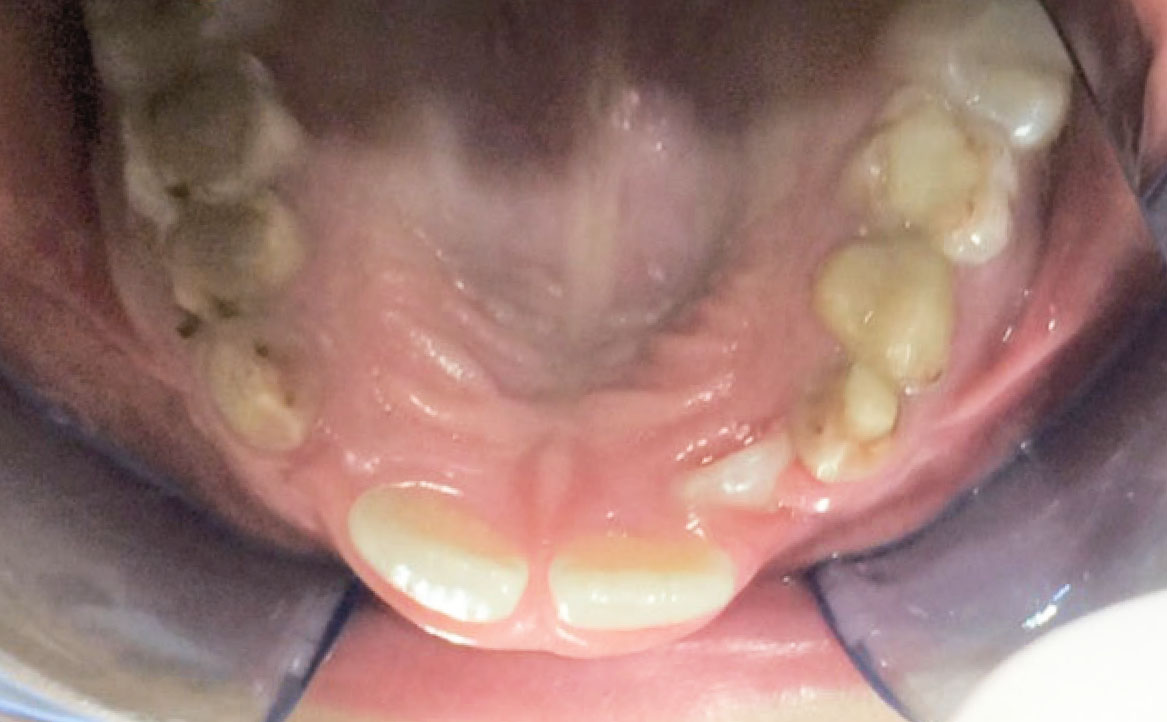

Dall’esame obiettivo intra orale si osservava una seconda classe canina destra e sinistra, una seconda classe molare destra e sinistra, e un diametro inter-canino e inter-molare ridotto sia in riferimento al mascellare superiore sia al mascellare inferiore (fig. 3A-3E).

Al fine di ottenere un’espansione delle arcate, nella fase iniziale, è stato posizionato un espansore rapido palatale sull’arcata superiore e un arco linguale a livello dell’arcata inferiore per permettere le estrazioni dei denti decidui compromessi.

A seguito del trattamento è stato osservato un miglioramento dell’igiene orale (fig. 5).